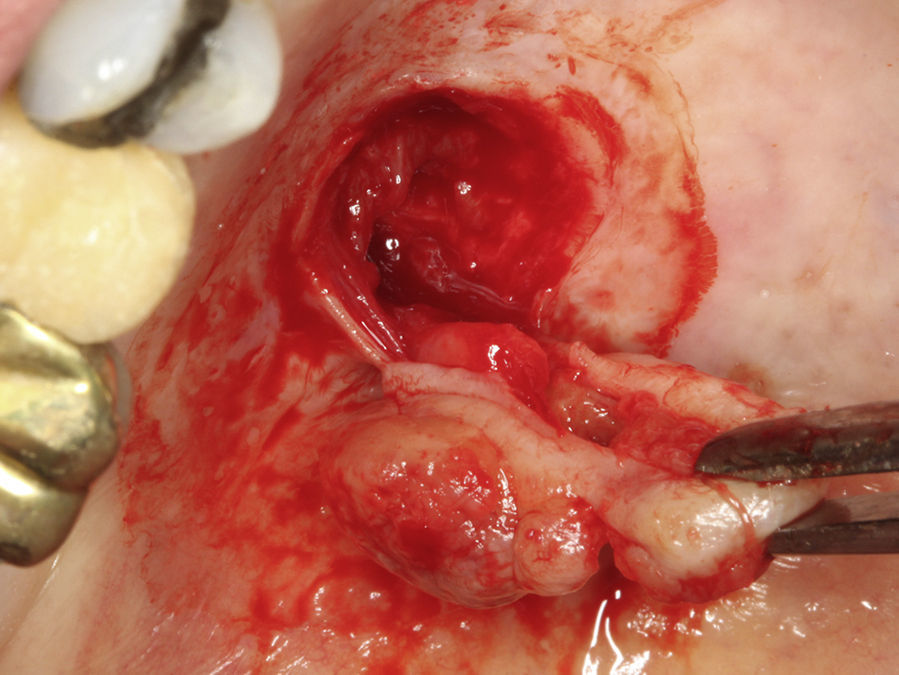

Casos clínicosCaso 1Paciente do sexo masculino, 68 anos de idade, leucoderma, procurou a Clínica de Estomatologia do Departamento de Odontologia da Pontifícia Universidade Católica de Minas Gerais (PUC Minas) queixando‐se de aumento de volume no palato, com tempo de evolução de 2 anos e discreta sintomatologia dolorosa. A anamnese não revelou alterações sistémicas. Ao exame clínico extraoral não foram observadas alterações. O exame clínico intraoral mostrou lesão nodular, pediculada, de consistência firme, localizada no palato duro do lado direito, entre os pré‐molares superiores e a rafe palatina, medindo aproximadamente 2cm na sua maior extensão. Foi realizada uma radiografia oclusal de maxila que não mostrou alterações ósseas. As hipóteses diagnósticas de neoplasia de glândula salivar e neoplasia mesenquimal benigna foram consideradas. Foi realizada biópsia incisional com diagnóstico anatomopatológico de adenoma pleomórfico. O tratamento proposto para a lesão foi a remoção cirúrgica conservadora. Paciente retornou após 4 semanas exibindo, ao exame intraoral, ulcerações na mucosa que recobria a lesão (fig. 1). Inicialmente, foi realizada anestesia local por meio da técnica supraperiosteal para bloqueio de ramos do nervo palatino maior, com cloridrato de lidocaína 2% e epinefrina 1:100.000 (ALPHACAINE 100®, DFL, Rio de Janeiro, Brasil). Em seguida, foi realizada incisão na base da lesão com bisturi lâmina 15 (Solidor, São Paulo, Brasil) e, após o descolamento do retalho mucoso palatino, a lesão foi exposta e removida (fig. 2). Foi realizada limpeza da ferida cirúrgica e sutura com fio seda Ethicon™ 4.0 (Johnson & Johnson, São Paulo, Brasil) (fig. 3). A lesão excisada (fig. 4) foi fixada em solução de formaldeído a 10% e enviada para exame anatomopatológico no Laboratório de Patologia Bucal da PUC Minas.

Paciente do sexo feminino, 31 anos de idade, leucoderma, foi encaminhada pelo cirurgião‐dentista à Clínica de Estomatologia do Departamento de Odontologia da PUC Minas para avaliação de lesão nodular no palato duro com diagnóstico histopatológico de adenoma pleomórfico, obtido por meio de biópsia incisional. Durante a anamnese, a paciente relatou a evolução da lesão há 4 anos com característica assintomática. Relatou estar no sexto mês de gestação e não apresentava outras alterações sistémicas. O exame extraoral mostrou ausência de alterações. Ao exame intraoral, observou‐se um aumento de volume bem delimitado no palato duro do lado direito, de consistência firme e coloração semelhante à da mucosa normal, medindo aproximadamente 2,5cm, exibindo pequena área de ulceração no local da realização da biópsia incisional (fig. 9). O exame radiográfico não mostrou alterações. O tratamento proposto foi a remoção cirúrgica conservadora e confecção de placa palatina em acrílico com grampos retentores para minimizar o desconforto pós‐operatório. Foi realizada anestesia local com lidocaína 2% e epinefrina 1:100.000 (ALPHACAINE 100®, DFL, Rio de Janeiro, Brasil), seguida de incisão semilunar com bisturi lâmina 15 (Solidor, São Paulo, Brasil) e rebatimento do retalho mucoso. Como a lesão se apresentava encapsulada, foi possível destacá‐la da mucosa suprajacente com facilidade (fig. 10). O retalho foi reposicionado por meio de pontos isolados (fig. 11) e a lesão (fig. 12) foi fixada em formaldeído a 10% para realização de exame anatomopatológico no Laboratório de Patologia Bucal da PUC Minas. Em seguida, foi colocada a placa de acrílico (fig. 13) para proteção da região operada e controlo da sintomatologia dolorosa.